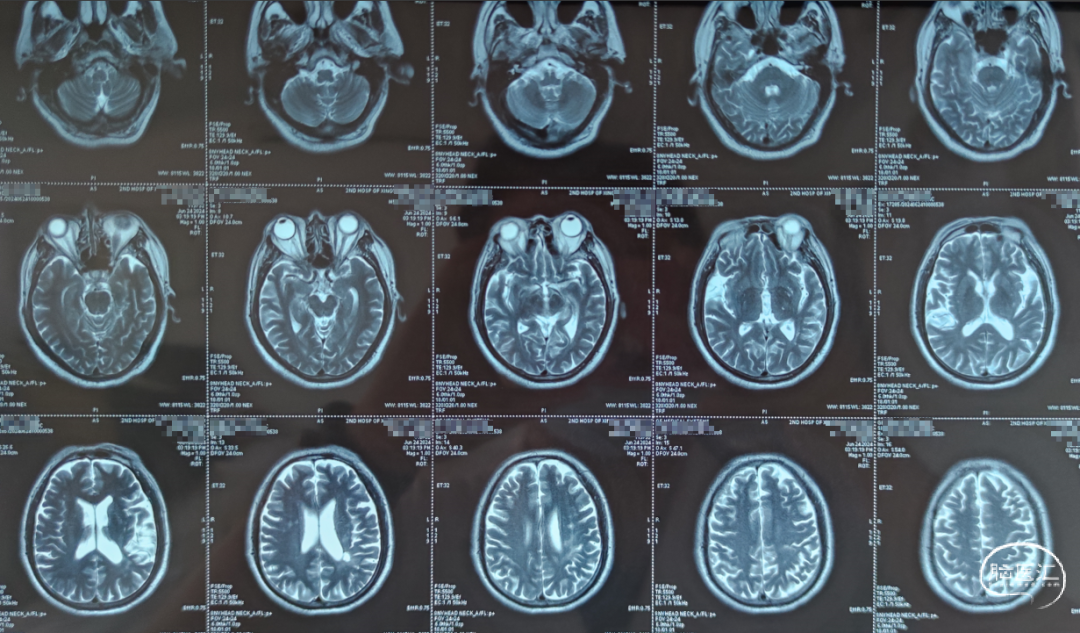

头颅MRI:未见新鲜脑梗死

DWI:

MRA:基底动脉重度狭窄